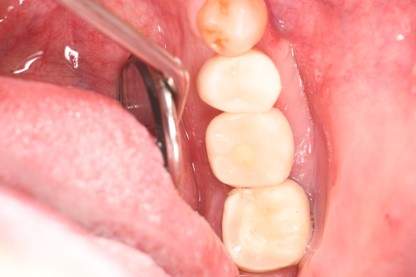

口腔内写真-3

| 年齢 | 40代・女性 |

|---|---|

| 主訴 | 右下7番 |

| 治療内容 | インプラント埋入 |

| 治療費 | インプラント埋入料 440,000円 GBR(骨造成) 110,000円 サージカルガイド 55,000円 2次OPE 22,000円 静脈内鎮静麻酔 77,000円 合計 704,000円 (2023年4月現在) |

| 治療期間 | 1年 |

| リスク・副作用 | インプラント手術は外科処置のため、一過性、場合によっては持続的に唇・舌・頬・口蓋・歯肉・歯牙等の感覚麻痺、切開に起因する瘢痕組織による知覚異常が起こることがあります。 インプラント手術ではドリルのようなものを使用するため接近歯の損傷が起こる事があります。 インプラント体と骨との結合不全が起こる可能性があります。 痛みや腫れは個人差もありますが、約1〜2週間程度続きます。痛みは痛み止めを服用することでしのげる程度です。 |

| 治療方針 | 右下7番は一度根管治療済みでその後痛みが出て保存不可能と判断し、抜歯を行いインプラントになりました。 骨が元々少ないので、インプラント埋入と骨造成は同時に行わず、骨造成を先に行い骨が出来るのを待ってからインプラント埋入を行う2回法で行いました。 |

| 特記事項 | インプラントは人工物なので虫歯になることはありませんが、歯周病(インプラント周囲炎)にはなります。インプラントを長持ちさせるには、毎日の歯磨きと合わせて、3〜6ヶ月ごとの定期検診でのクリーニングが大切です。 |

| 担当者所見 | かみ合わせが強くマウスピースを進めましたが、本人はマウスピースが難しいため今後ボットクスで様子を見ていきます。 |